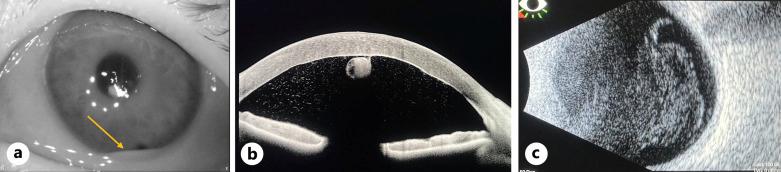

CASE PRESENTATION

A 67-year-old female with a prior ocular history of bilateral cataract surgery, Fuchs endothelial dystrophy, and pseudophakic DMEK in the left eye presented with endophthalmitis 2 months after keratoplasty. DMEK graft removal without replacement with an intracameral washout, pars plana vitrectomy, intracameral, and intravitreal antibiotics resulted in an excellent visual outcome (20/25).

CONCLUSION

This is a unique case of late endophthalmitis following DMEK surgery requiring graft removal and pars plana vitrectomy with excellent visual recovery without donor replacement.